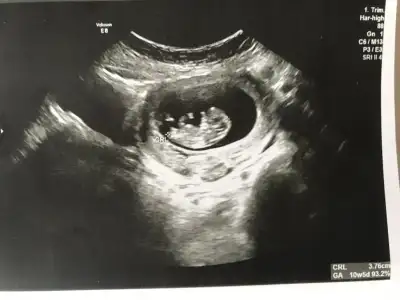

O gözüken nub mu emin olamadım ama yine de bir atayım belki fikir yürüten olur didimm.

10+5 günlük bir kurbağa 🐸 🐣

Ne dersiniz?? Ikra meyra Ikra meyra